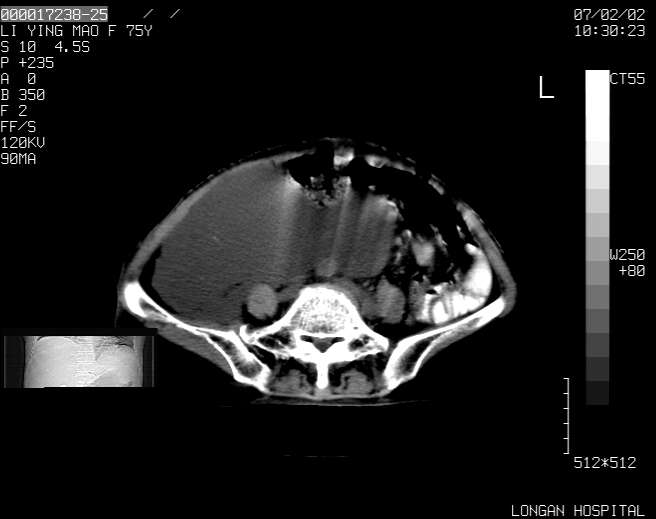

以下是引用dyqct在2007-2-10 8:53:00的发言:[br]考虑:1、肝脏多发囊肿[br] 2、左肾囊肿,右肾多发结石并积水。[br] 3、右胸少量积液。[br] 4、右肾周包裹性积液或淋巴管瘤(有见缝就钻的征象、薄隔、小结节状钙化)?[br] 5、腰椎动脉瘤样骨囊肿?[br] [br] [br]